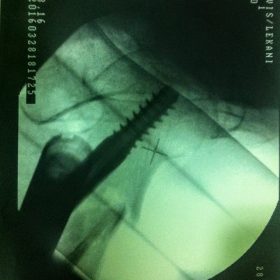

Διατροχαντήριο : Εξωαρθρικό κάταγμα, στην περιοχή ανάμεσα στο ελάσσονα και το μείζονα τροχαντήρα. Αντιμετωπίζεται χειρουργικά με ενδομυελική ήλωση τύπου γ-Nail. Δύο τομές 3 εκατοστών και 1 εκατοστού αντιστοίχως για την εισαγωγή και το κλείδωμα του ήλου μέσα στο οστό. Η μέθοδος είναι κλειστή,σχεδόν αναίμακτη,διάρκειας 30 λεπτών,με τη βοήθεια C-ARM (τηλεόρασης). Στον ασθενή παρέχεται οπτικό υλικό (όλα τα χειρουργικά στάδια) σε CD ή Στικάκι,λόγω της δυνατότητας καταγραφής του χειρουργείου από το C-ARM Ο ασθενής περπατάει άμεσα μετεγχειρητικά στις 5 ώρες μετά την επέμβαση και εξέρχεται από το νοσοκομείο σε 1 -2 ημέρες.